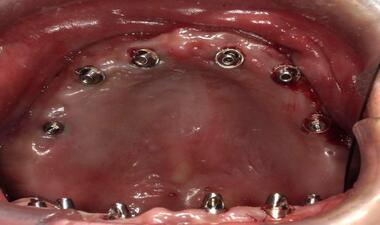

術中

上顎缺牙,植入六顆植體